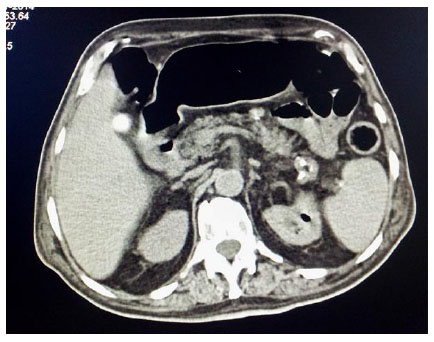

An elderly gentleman, aged 83 years, with diabetic end-stage renal disease, who was on maintenance haemodialysis, complained of severe pain in both the thighs when he came for his scheduled dialysis. He reported that the pain was severe, and he was unable to walk and attend his activities of daily living (ADL). He presented no history of fall or fever. He had been receiving twice weekly haemodialysis through left brachiocephalic arteriovenous fistula for the last one year. His regular medications included human premixed insulin 8 units daily, sustained release of Nifedipine 20 mg twice daily along with tab calcium carbonate and vitamin supplements.He was ambulatory and required no assistance for ADL earlier. His diabetic status and blood pressure were fairly under control till this event. Examination revealed no inflammatory signs. There was no evidence of fracture clinically and he was prescribed some anti-inflammatory drugs. He returned for his scheduled dialysis again after three days complaining of persistent pain. He appeared sick, but was stable hemodynamically. He was in severe agony with his slightest movement.There was local tenderness but no other inflammatory signs. He could complete haemodialysis without event and refused further investigations. He returned for the scheduled dialysis again after three days. This time, he reported fever with chills for two days prior to the hospital visit and presented in a moribund state. He was febrile and had excruciating pain in both the thighs. The slightest movement of lower limbs caused him severe pain. His vitals included BP of 180/110 mm of Hg, pulse rate of 130 beats/min and respiratory rate of 24 cycles per minute. He was conscious and fully oriented. He had severe tenderness in the lower abdomen and in both the thighs with no other inflammatory signs.Laboratory investigations revealed haemoglobin 11.1gm/dl, total leucocyte count 24300 cells/cu mm with polymorphonuclear neutrophil predominance and a platelet count of 213000 cells /cu mm. Random blood sugar was 501 mg/dl. Serum creatinine, calcium and phosphorus were 6.4, 9.8 and 5 mg/dl, respectively. He had normal serum electrolyte and uric acid. ABG revealed metabolic acidosis with a pH of 7.21 and serum bicarbonate being 11.2 mmol/l. Liver function test was normal except serum albumin of 3.0 g/dl. Urine was negative for ketones but microscopic examination showed 20-25 pus cells and red blood cells. Urine and blood culture both grew Escherichia coli. His chest X ray was normal. Ultrasound examination of the abdomen showed the presence of gas in the bladder and due to disproportionate symptoms, non-contrast CT scan abdomen was ordered. The CT scan revealed extensive mottled air pockets in the muscles of bilateral upper thigh, predominantly involving adductor compartments, right more than left Fig. (1). There was thickening of the urinary bladder wall with perivesical fat stranding and intramural as well as intraluminal air consistent with emphysematous cystitis Fig. (2). Mild left emphysematous pyelonephritis was also noted Fig. (3). He was treated with IV meropenem and Levofloxacin. Foley’s catheter was inserted for bladder drainage. Insulin infusion was started. However, he weakened quickly, became hypotensive and disoriented. Following this, haemodialysis was intensified, so he was treated with inotropic infusions and other supportive measures.The patient’s family refused surgical options.He succumbed 4 days after admission.